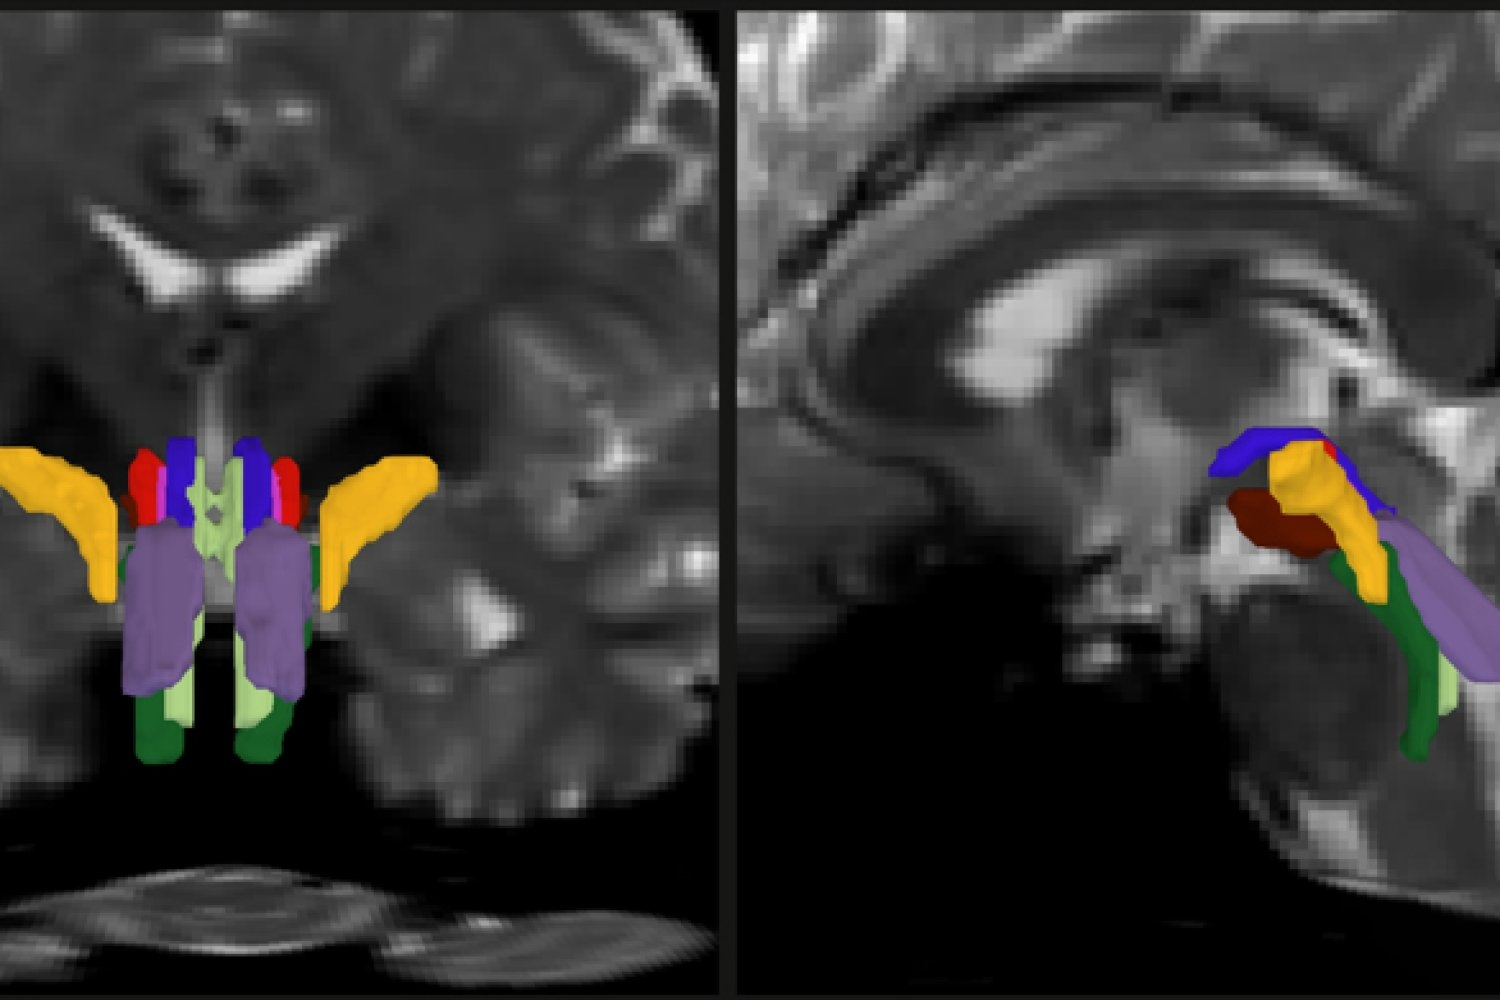

However, imaging the brainstem posed significant challenges due to its small size and its close proximity to pulsating fluids and moving organs. This is where the AI model steps in. It uses a convolutional neural network to analyze diffusion MRI scans, creating a probabilistic map of fiber pathways that descend into the brainstem. It then delves deeper to identify eight specific white matter bundles within the brainstem.

For BSBT to become a reliable tool, it had to be put through rigorous testing and validation. Olchanyi trained the system using 30 annotated diffusion MRI scans from the Human Connectome Project. The tool’s accuracy was then cross-verified by comparing its results with data from post-mortem brain dissections and ultra-high-resolution scans. BSBT’s reliability was confirmed when it successfully identified the same bundles in repeated scans of the same individuals.